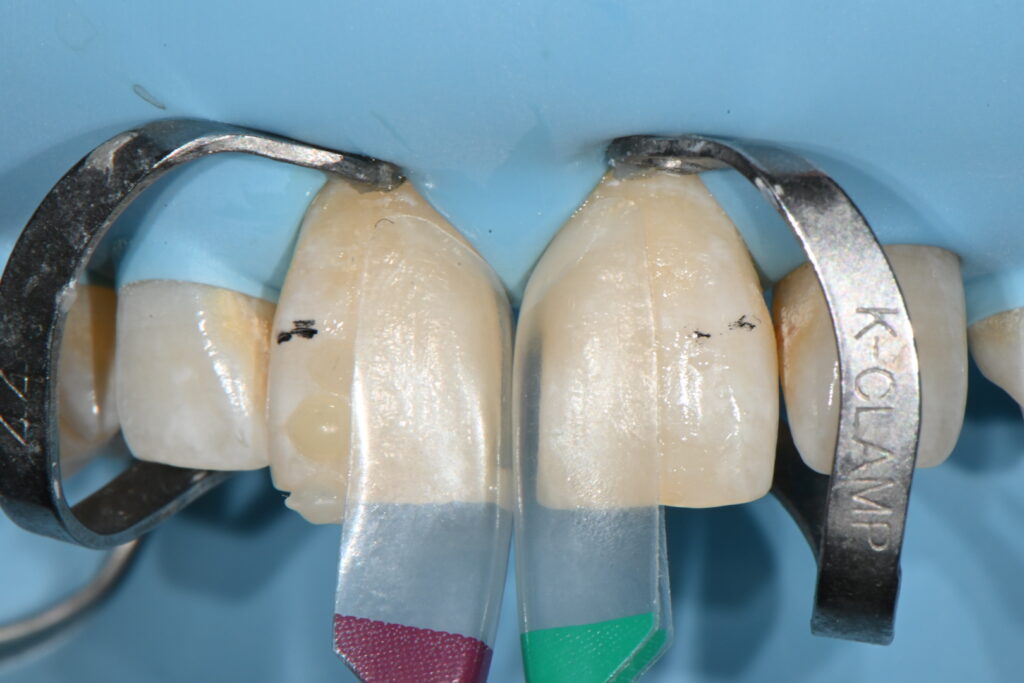

하나씩 재현해 나가는 과정입니다

바이오클리어만으로 할수 있는 치료는 아니구요

수많은 조합이 있기 때문에 여기서 술자의 노하우가 필요한 치료 과정입니다

그리고 시간이 굉장히 많이 소요되는 술식입니다

1차적인 형태가 잡히는 과정입니다

대햑적인 형태를 잡고 그리고 길이 모양 형태를 수정합니다